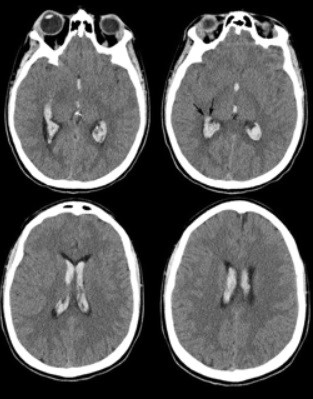

Se pueden mencionar al respecto los estudios que han encontrado en pacientes dependientes al alcohol una disminución del volumen de sustancia gris en el área de la corteza frontal, el hipocampo y el tálamo. El volumen de las sustancias blanca y gris también se puede ver disminuido en el área periventricular, la protuberancia y el cerebelo. Estos déficits de volumen también se han localizado en la corteza prefrontal dorsolateral derecha, ínsula anterior derecha, en el núcleo accumbens y en la amígdala izquierda(16) (ver Imagen 1).

Asimismo, como se indicó previamente, a través de la TC también se puede observar el deterioro de la microestructura cerebral por adicción al alcohol. El abuso de esta sustancia altera cinco fibras del cerebro, como el cuerpo calloso, el fondo de saco, la cápsula externa, el cíngulo circunvolución y el fascículo longitudinal superior, las que están involucradas en funciones como el procesamiento visoespacial y del lenguaje, la comunicación interhemisférica, la memoria, el procesamiento emocional, la toma de decisiones y la integración sensorial(16) (ver Imagen 2).